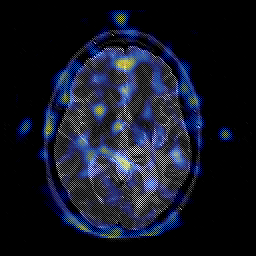

Glioblastoma multiforme overlay -- Slice #27

[Home][Help][Clinical][Tour 1][Tour 2][Tour 3] Slice 27